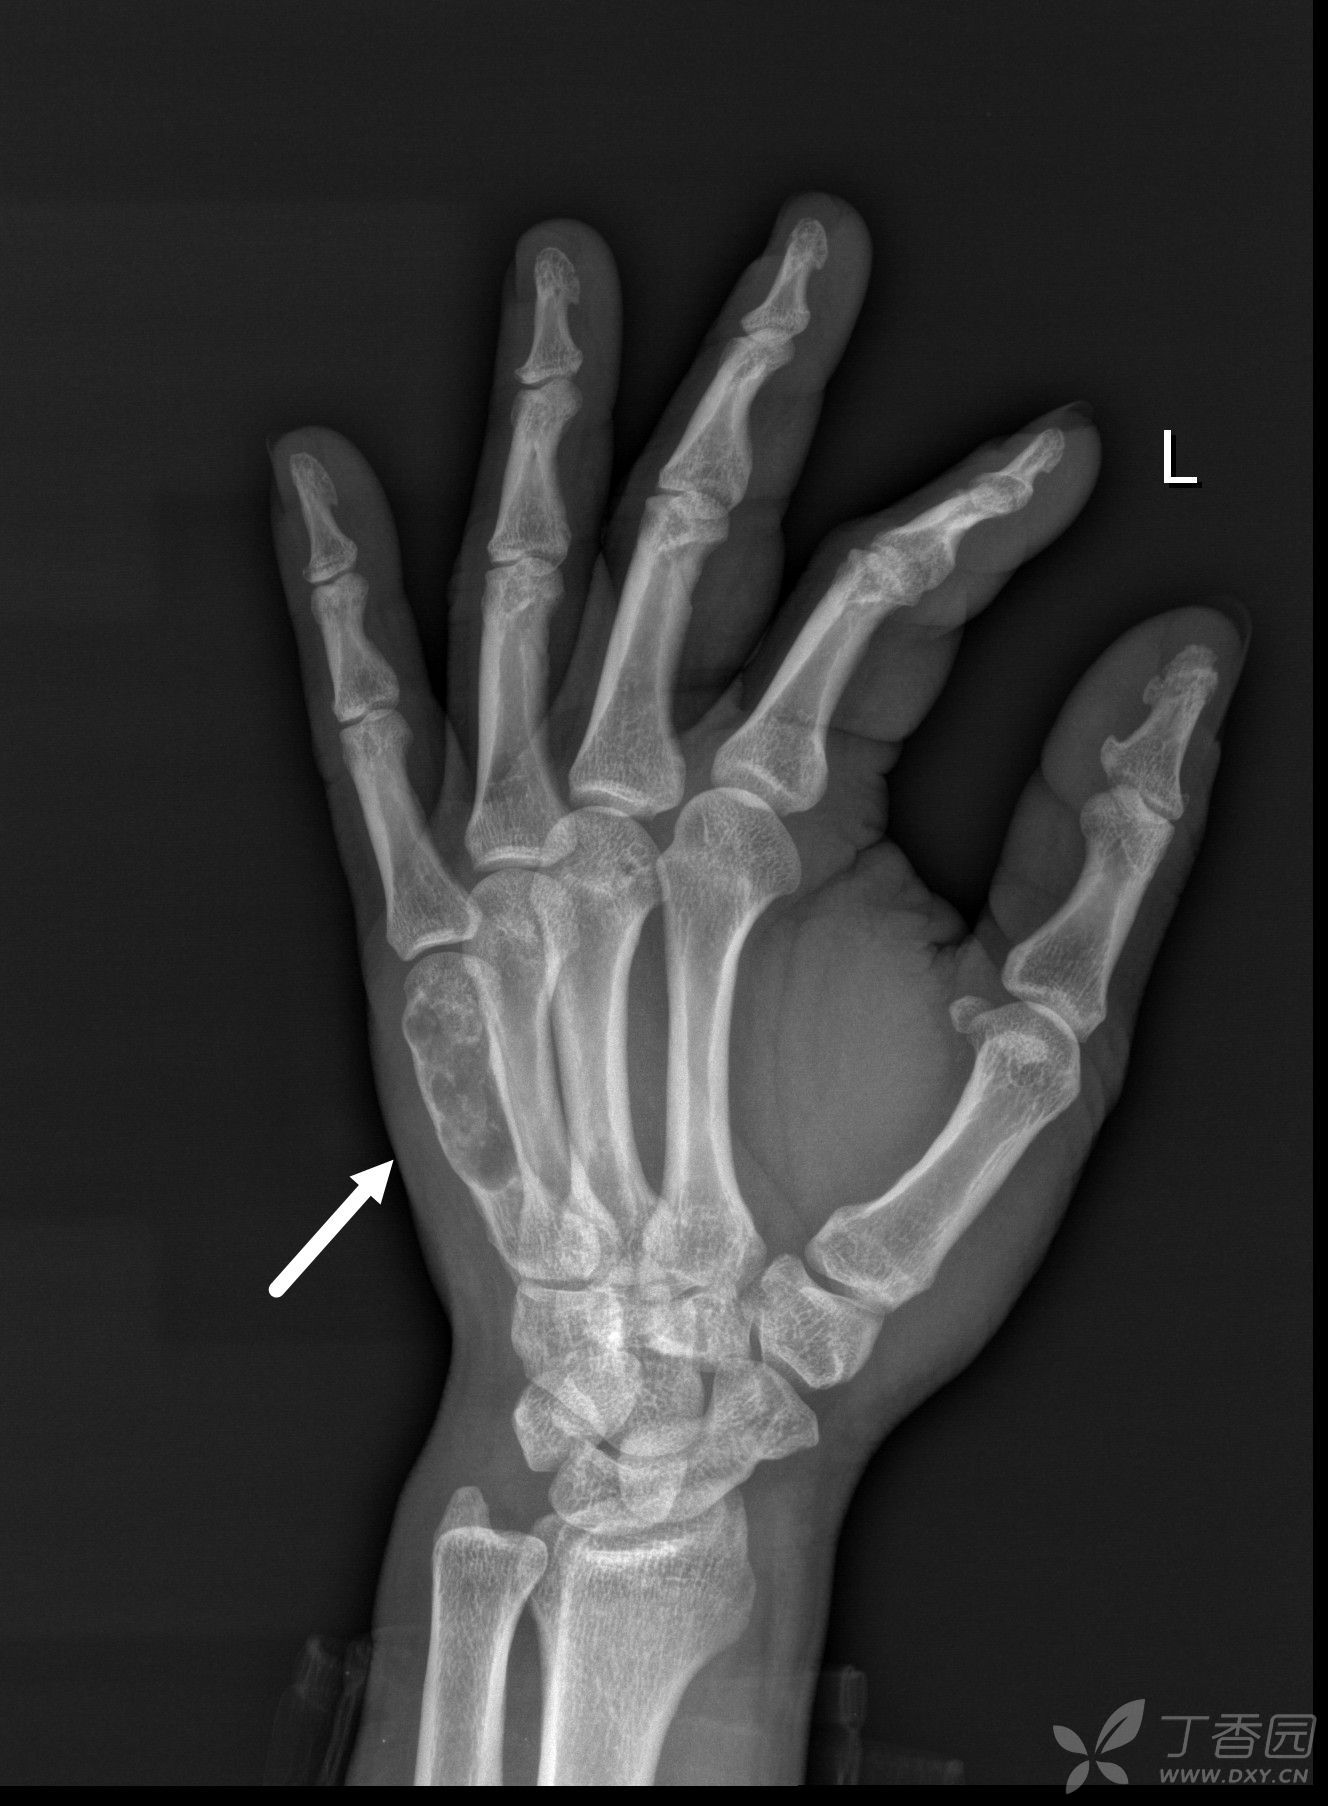

内生软骨瘤?

内生性软骨瘤病是一组少见的,位于骨髓腔内的多发性良性软骨性肿瘤.